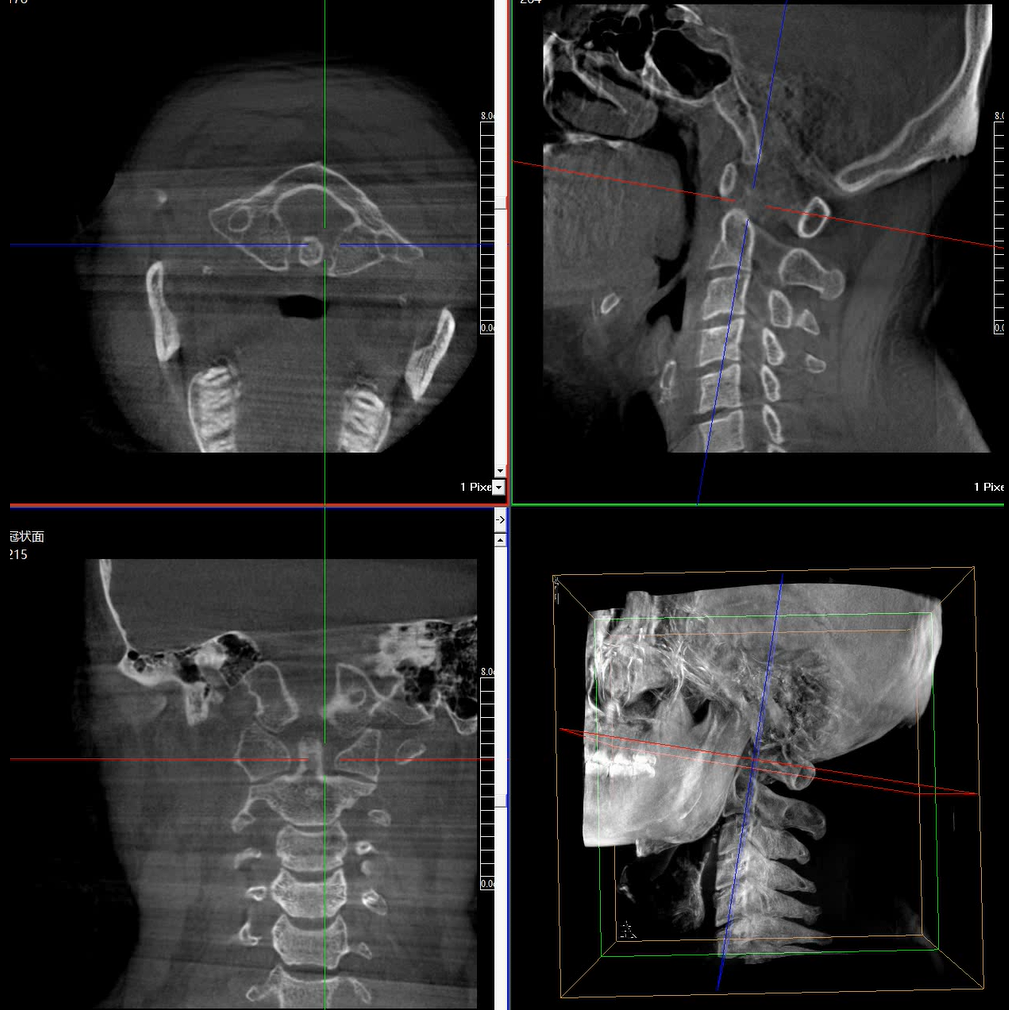

術(shù)中三維成像和橫斷面圖像提供多角度的手術(shù)診斷信息,輔助醫(yī)生進(jìn)行術(shù)中評(píng)估判斷,諸如骨折復(fù)位情況和內(nèi)植入螺釘?shù)某叽绾臀恢?,輔助手術(shù)更好地完成。

提供更大的術(shù)中三維成像視野,采集更多圖像信息,可一次拍全全段頸椎、全段腰椎、七節(jié)胸椎、雙側(cè)骶髂關(guān)節(jié)、股骨頭及單側(cè)盆骨。

在C臂掃描過(guò)程中,始終保持拍攝主體處于射線束的中心,避免了序列圖像采集過(guò)程中的橫縱方向運(yùn)動(dòng),減少相對(duì)運(yùn)動(dòng)造成的運(yùn)動(dòng)偽影。